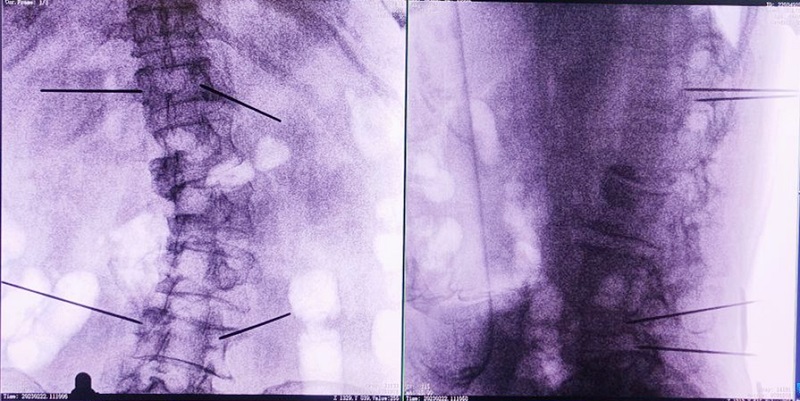

機器人輔助下椎體成形術,是以手術機器人智能機械臂為基礎,仿照經皮骨水泥椎體成形術的施術步驟,限定穿刺點、穿刺方向、角度和深度,使穿刺針經過安全路徑進入目標區域,然后進行骨水泥注入,輔助手術設計、精準指導手術實施。以普愛醫療的骨科手術機器人PL300B為例,其輔助進行的一例胸腰椎壓縮性骨折經皮椎體成形術的過程如下:

(3)根據設定好的的位置和入針方向,植入引導針;

(4)所有引導針植入完畢后,沿引導針方向進行椎弓根及椎體置管,建立通道;